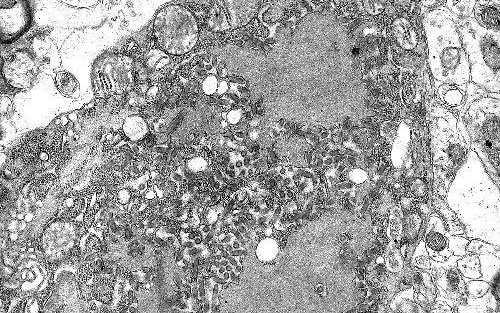

科学家于1967年发现了马尔堡病毒,当时德国的实验室人员由于接触了来自乌干达的感染猴子而造成了小范围的感染爆发。马尔堡病毒与埃博拉相似,都能造成出血热,也就是感染后表现出发热和内出血症状,这又会导致休克,器官衰竭和死亡。

第一次已知的埃博拉感染人类同时发生在1976年的苏丹和刚果民主共和国。埃博拉通过接触血液或其他体液,感染者的组织进行传播。Muhlberger表示,已知毒株的致死率有大有小。

比如,Reston埃博拉,甚至无法使人生病。但是Bundibugyo埃博拉的致死率有50%,Sudan埃博拉已经上升到71%。